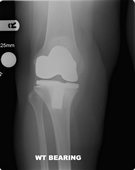

Knee replacement involves replacing the worn out knee joint. The end of the femur is resurfaced with a metallic component, a tray is placed on the tibia and a polyethylene spacer is inserted between the two components. For most total knee replacement the under surface of the kneecap is re-surfaced with a small polyethylene button.

In contrast to the hip joint the knee joint is made up of three parts or compartments. The inner (medial) and outer (lateral) halves and the patello-femoral joint (knee cap), it is possible to replace these separate components in isolation, depending of the type and pattern of arthritis the patient has.